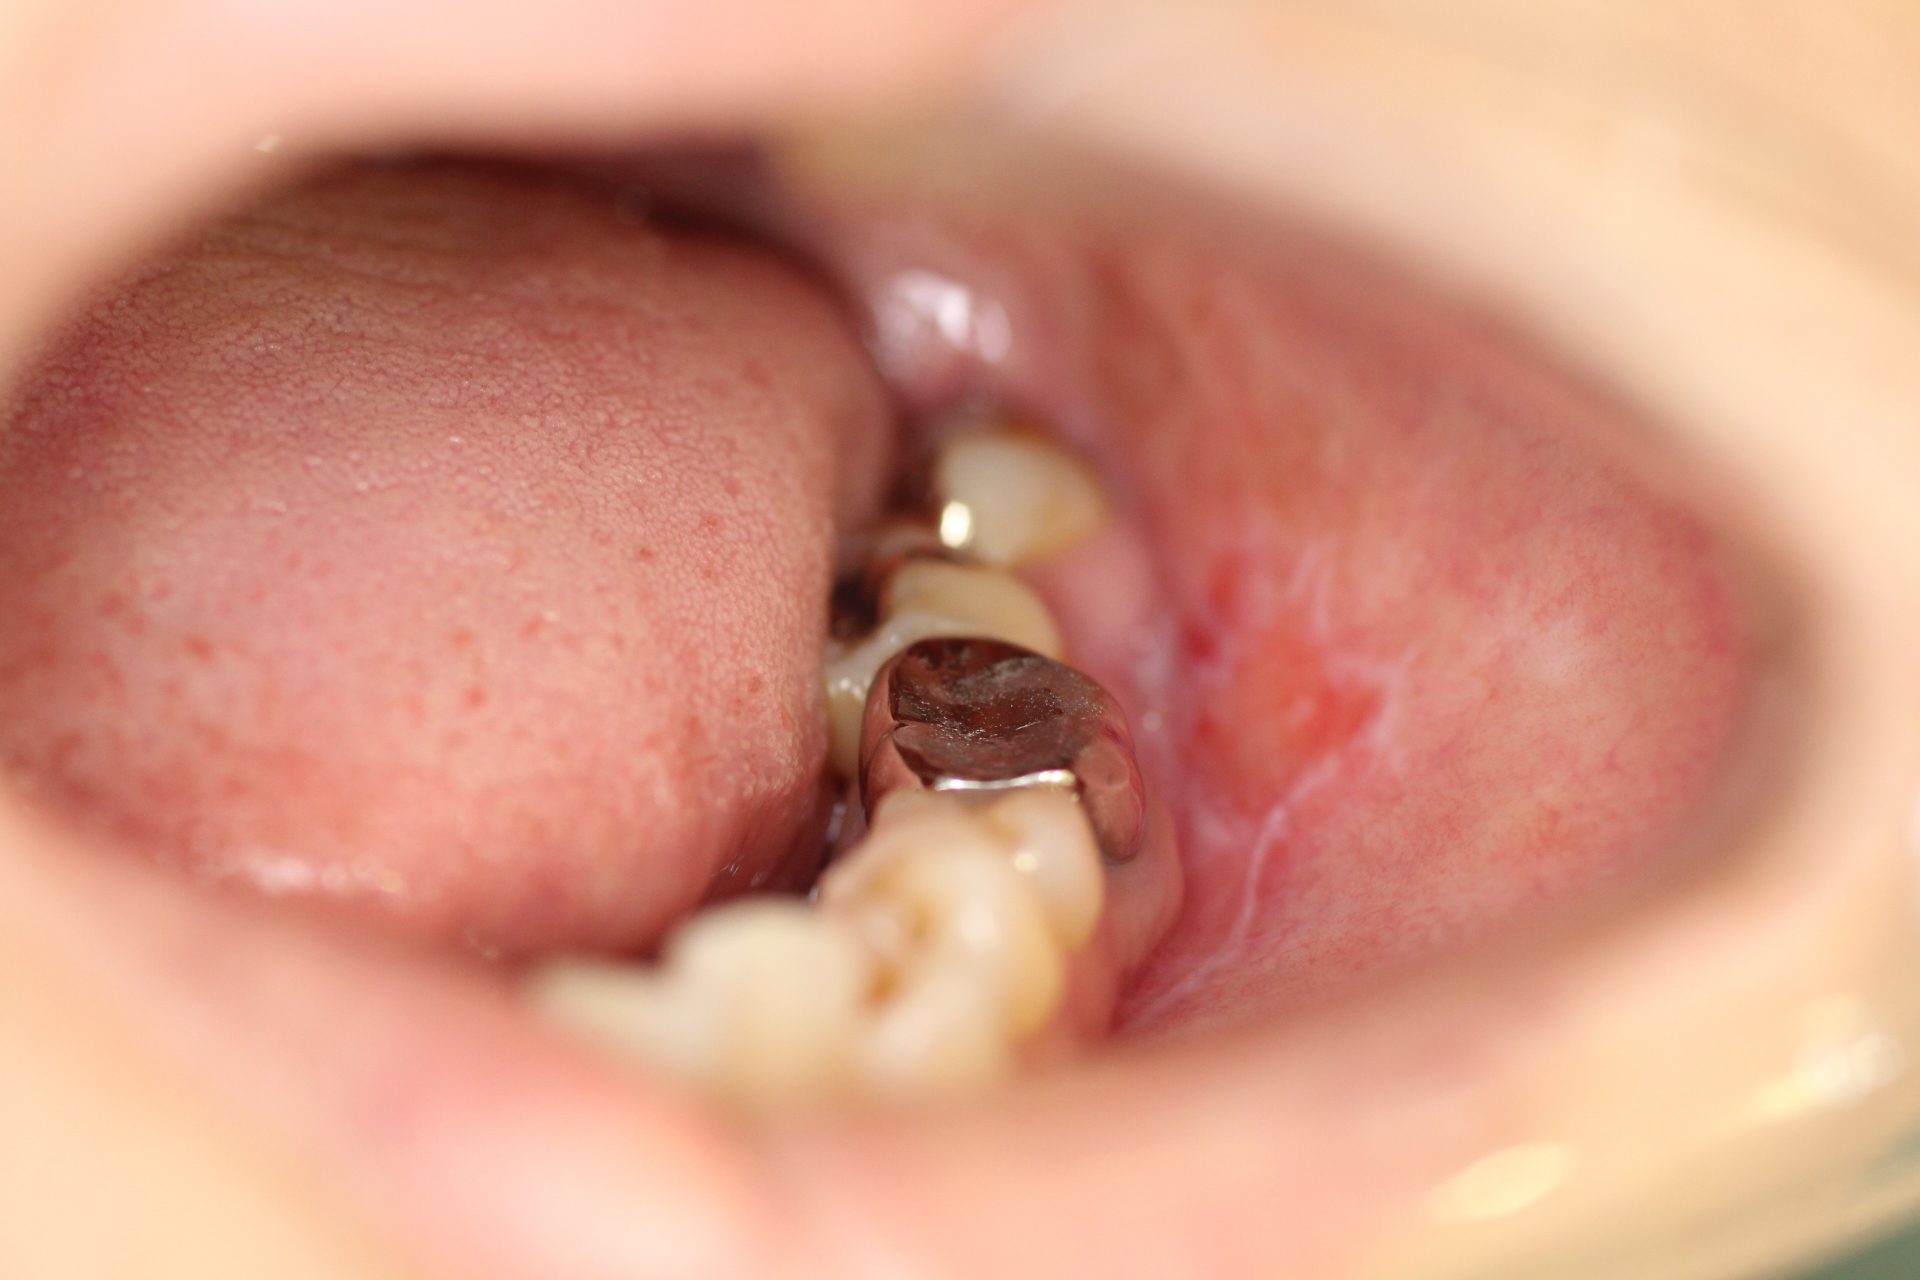

扁平苔癬による歯肉の発疹と腫れを歯周病治療で改善した症例木村歯科医院羽生市の痛くない歯科治療・予防歯科・審美歯科・インプラント。